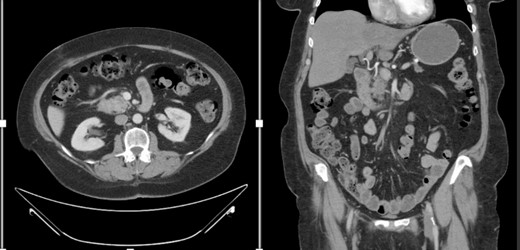

She underwent an open pylorus-preserving pancreatoduodenectomy with segmental superior mesenteric vein resection with primary reconstruction (ISGPS Type 3) without complication. Final pathology demonstrated a 3.6-cm poorly differentiated adenosquamous carcinoma with SMV invasion into the intima (Fig. 2), 1 of 24 regional lymph nodes with metastatic carcinoma, lymphovascular and perineural invasion (Fig. 3), and an 85% squamous differentiation (Fig. 4). There was a partial pathologic response (College of American Pathologist Grade 2) within the primary tumor and involved lymph node tumor [7]. There was noted to be tumor extension within 1 mm of the superior mesenteric artery margin (Fig. 5) (R1 status) with negative additional margins. She recovered without complications and was discharged home on the fourth post-operative day. Repeat staging CT imaging demonstrated no evident disease. She was initiated on adjuvant systemic therapy.

Adenosqumous carcinoma with both components (adeno and squamous) A19 Cytokeratin 7 immunostain, highlighting the adenocarcinoma, and p40 immunostain, highlighting the squamous carcinoma component